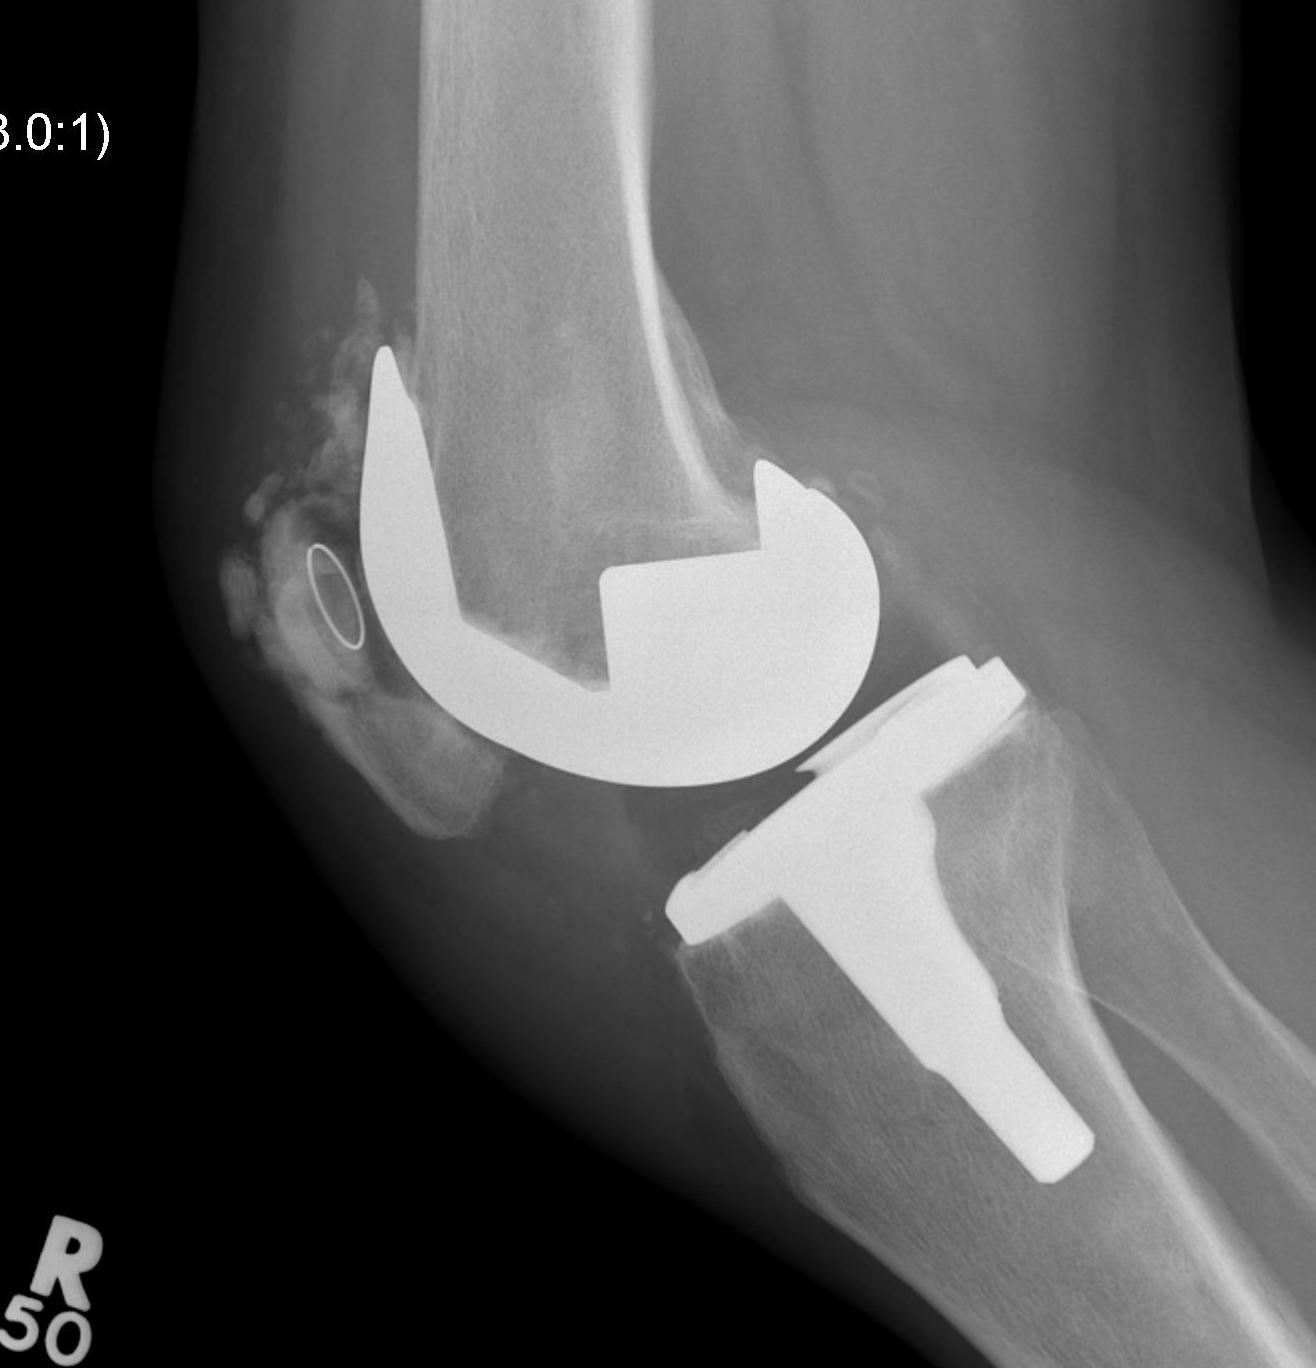

Xray

- skyline views

- lateral tilt / subluxation